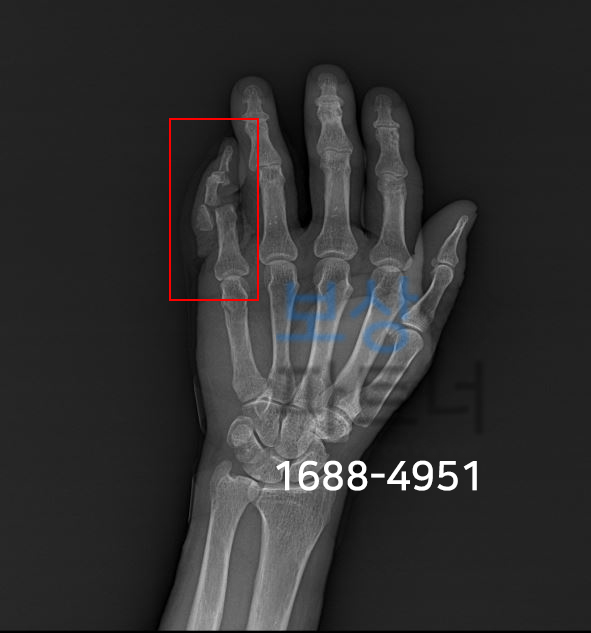

사고 당시 손가락의 엑스선 사진입니다.

김@@님은 5수지의 뼈들을 올바른 자리로 정복하고 핀으로 고정하는 수술을 받으셨죠. 하지만, 수술일 잘 되었음에도 향후 장해의 잔존 가능성을 배제할 수 없었습니다. 오늘의 사례는 단순히 진단서나 입퇴원확인서를 발급받아 청구하면 나오는 보험금 소개가 아닙니다.